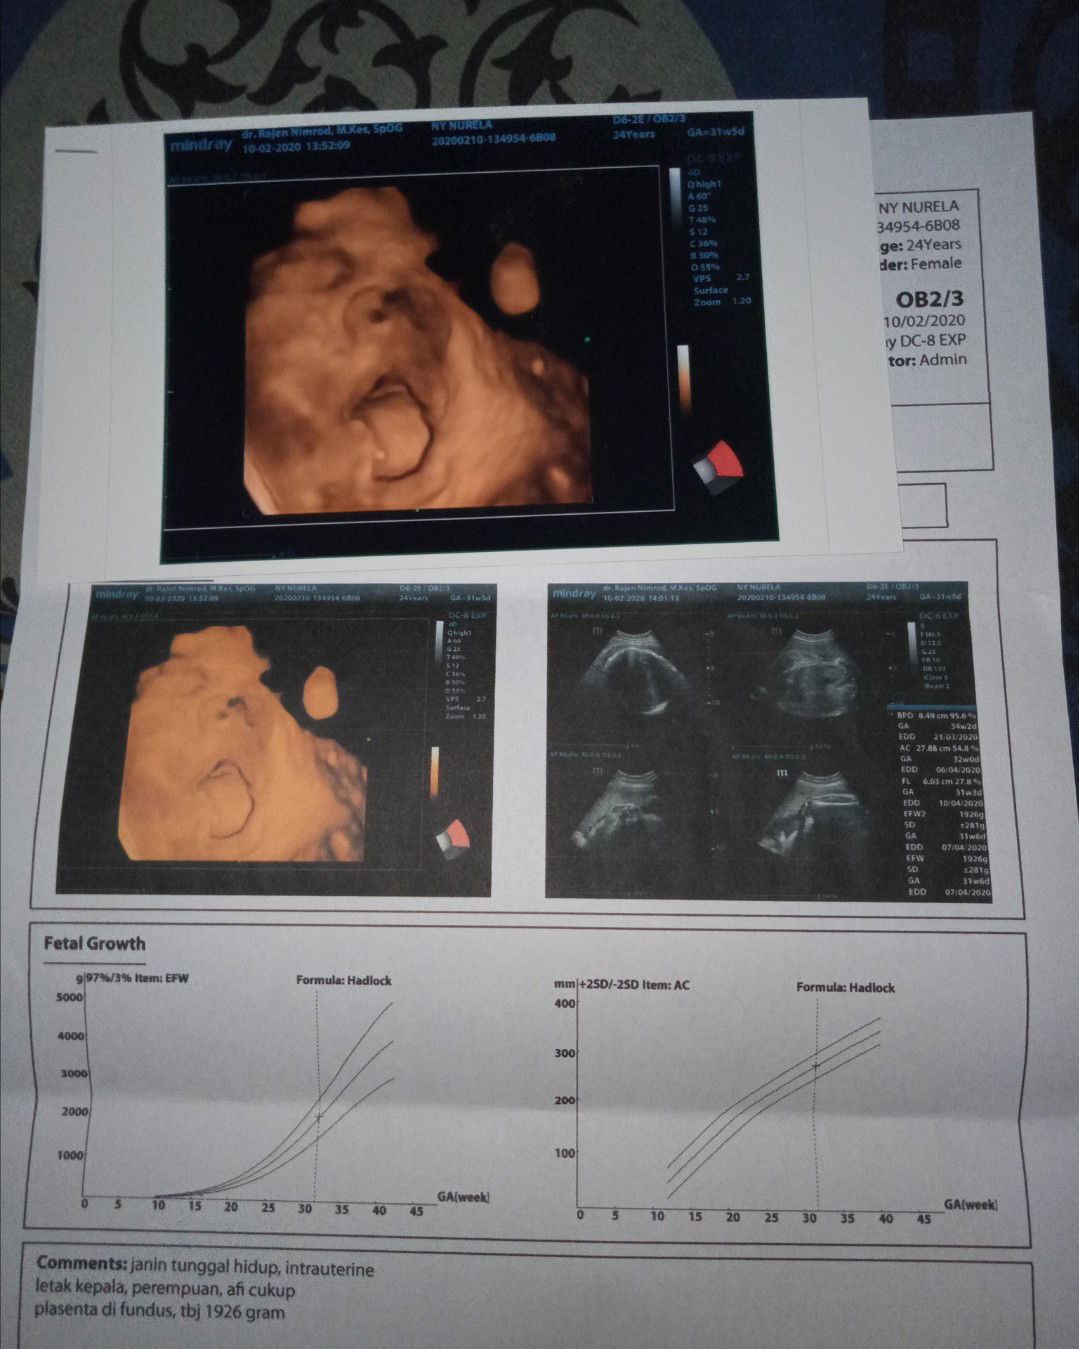

Bunda agak sedikit sedih sih dek , karena kamu nongol ga seperti yg bunda harepin ( keliatan wajah yg utuh ) ? , kata dokternya si karena kamu udah kegedean di dalem, jd udh susah ketangkep kamera ???♀ tp gpp ya dek meskipun begitu Alhamdulillah kita berdua sehat & Mudah²n sehat terus serta lancar sampe kita bertemu nanti Aamiin ?? by the way, itu ekspresi dede kok gitu si, hihihi bikin gemes ayah bunda aja, jdi makin ga sabar buat cepet ketemu ? laper ya dek ga sabar mau 'enen , apa ga sabar mau minta jajan ? Btw bun mau nanya, di Usia kehamilan aku yg 31weeks5days ini Berat Badan Janin nya 1926 gram, itu sesuai ga ya bun? ( kalo pas aku nanya ke dokternya sih sesuai, tapi aku pengen lebih tau lagi dari para bunda disini ? )

Periksa kehamilan di Usia 31weeks3days Tensi darahku 110/80 .. Itu bagus ga bun ?